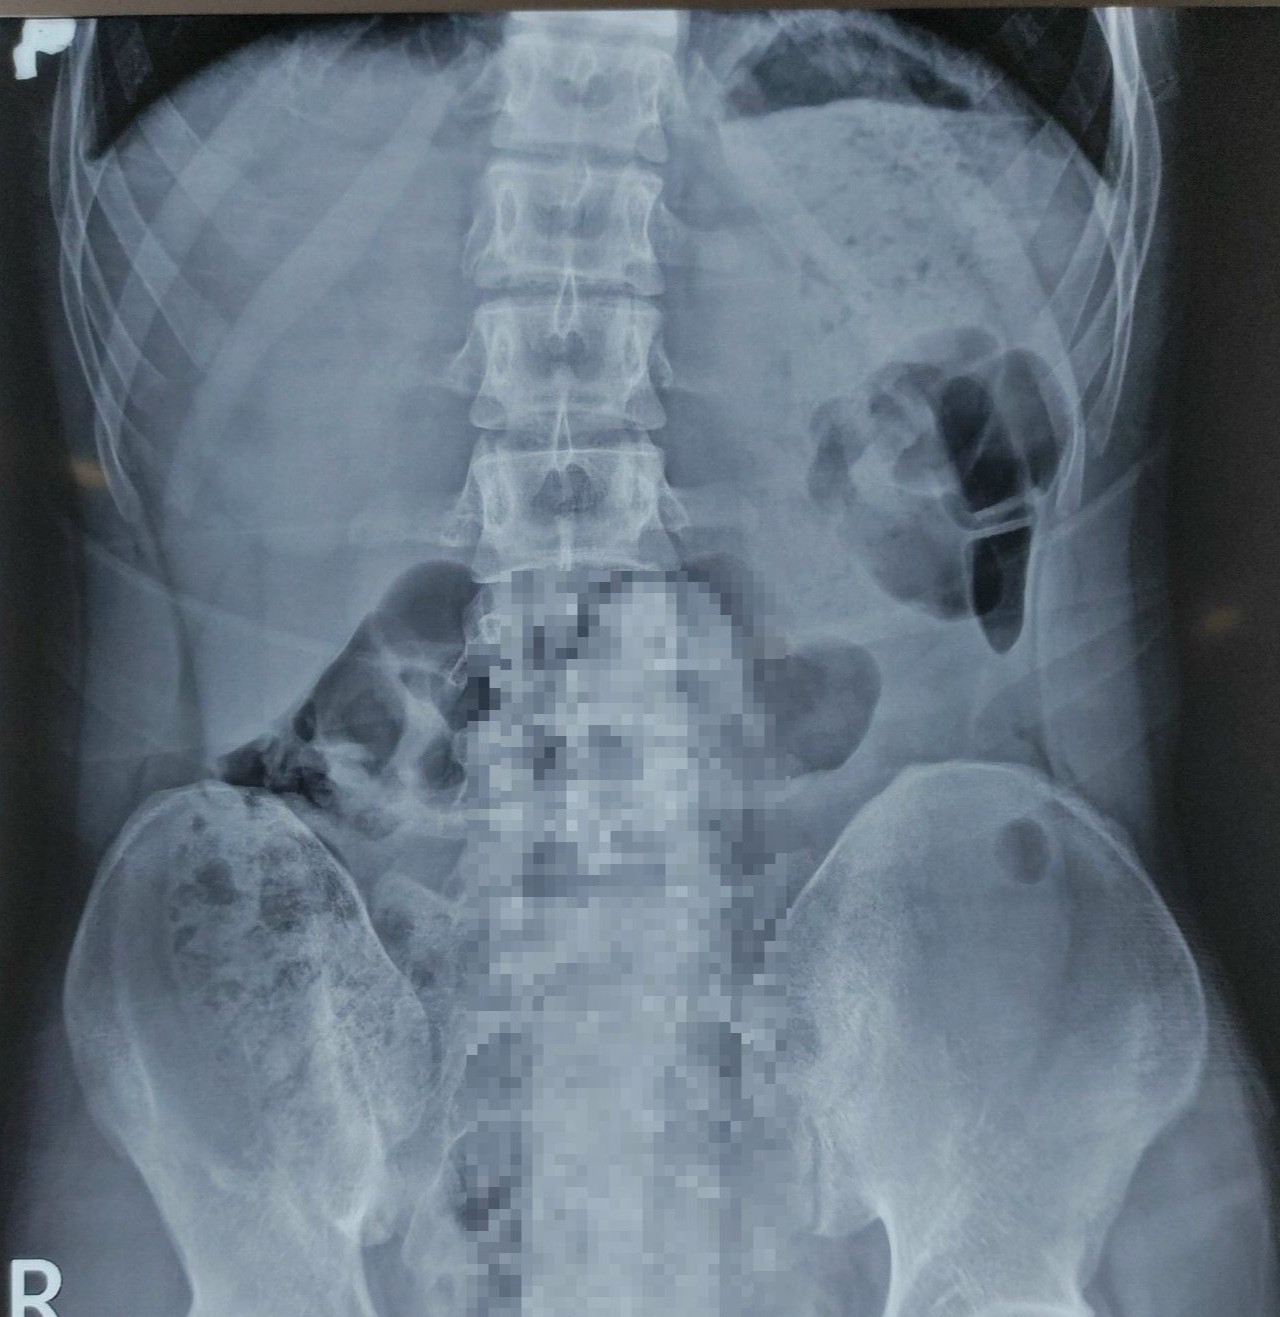

Bệnh nhân được đưa đến Khoa Cấp cứu, Bệnh viện Quân y 175. Qua thăm khám và chụp X-quang, bác sĩ phát hiện có dị vật hình dạng giống “dương vật” nằm sâu trong trực tràng. Do đó, bệnh nhân được chuyển lên Khoa Phẫu thuật - Gây mê hồi sức để tiến hành lấy dị vật.

Sau 30 phút, bác sĩ chuyên khoa ngoại tiêu hóa đã lấy thành công dị vật bằng dụng cụ qua đường hậu môn, không cần phẫu thuật. Dị vật là một dương vật giả kích thước 25x5cm. Bệnh nhân được xuất viện ngay trong ngày trong tình trạng sức khỏe ổn định.